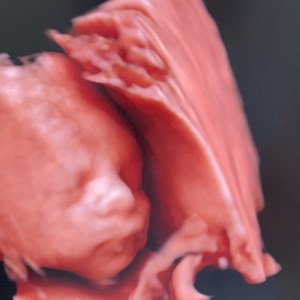

Hjertelyd - scanningsklinik for gravide

Sødeste lille nus 😍 Denne pige var på besøg i dag - hendes mor og far samt mormor og far...

Lørdagens sidste besøg. En flok glade piger(og én lille baby dreng) til Baby-shower 🩵👶�...